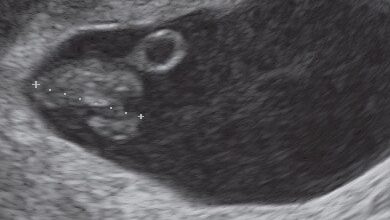

Primera ecografía con 2 semanas: el embrión es visible bajo la forma de una pequeña vesícula de 3 mm de diámetro. Este está implantado en el endometrio (músculo uterino presente en toda la periferia).